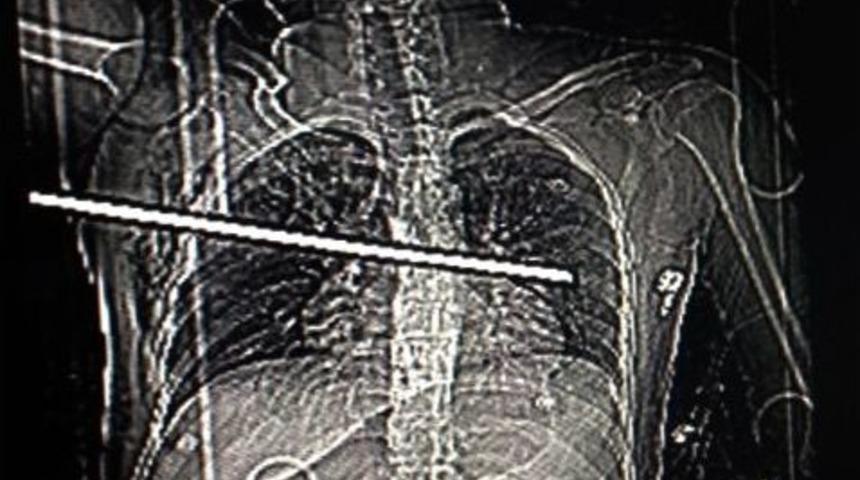

Alınan bilgiye göre, Sultanbeyli’de bir inşaatta çalışan üniversite öğrencisi Serkan Kara (28), dengesini kaybederek üçüncü kattan kolon demirlerinin üzerine düştü. Demirlerden biri Kara’nın sağ kolunun altından girerek, göğsünü deldi. Olay yerine çağrılan itfaiye ekipleri, yaklaşık bir saat süren çalışmanın ardından demir çubuğu kesti. Kartal Eğitim ve Araştırma Hastanesi’ne kaldırılan genç, ameliyata alındı. 35 santimlik demirin, sağ akciğeri parçalayıp kalp zarını zedeleyerek sol akciğere hasar verdiği, kaburga kemiklerinde de hasar oluştuğu belirlendi. Doktorların çift taraflı ameliyatı ile, demir saplandığı yerden çıkarıldı. Yaklaşık 2 saat süren ameliyatın ardından 2 gün yoğun bakım ünitesinde kalan Serkan Kara, hayati tehlikeyi atlattı.